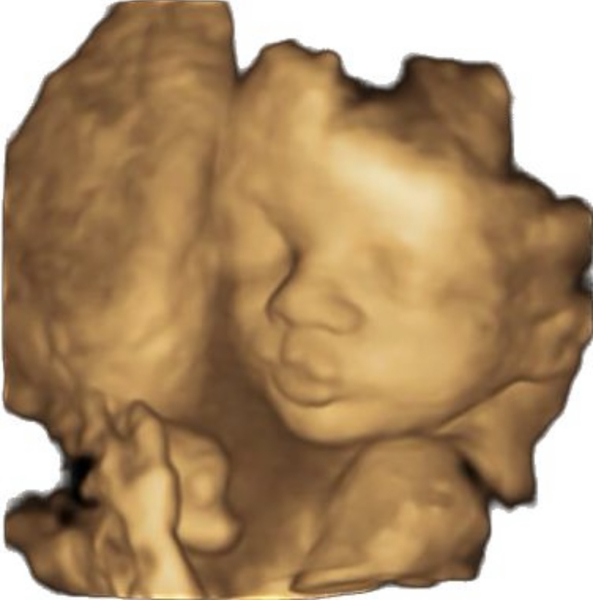

Katlouise24 · 10/12/2022 14:26

We got our 4D scan too! We got a cheeky girl by the looks of her sticking her tongue out! Haha, all she did was yawn too🥹